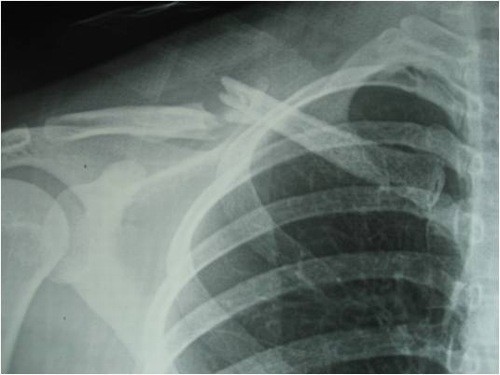

Gãy xương đòn là một chấn thương thường gặp với tần suất khoảng 1/1000 mỗi năm và chiếm 2.6% đến 5% các trường hợp gãy xương. Hầu hết gãy xương đòn xảy ra ở nam trước 25 tuổi, sau đó giảm dần và rất ít gặp ở tuổi 35-55 rồi tăng dần trở lại. Ở phụ nữ, tần suất gãy xương đòn ở người dưới 25 tuổi và trên 75 tuổi là như nhau

Gãy 1/3 giữa xương đòn chiếm tỷ lệ 69%- 82% tất cả các trường hợp gãy xương đòn. Gãy 1/3 giữa xương đòn thường gặp ở trẻ em và thanh niên với lực chấn thương có năng lượng cao gây gãy nhiều mảnh, di lệch nhiều.

Gãy xương đòn cần được phát hiện sớm và điều trị kịp thời hiệu quả